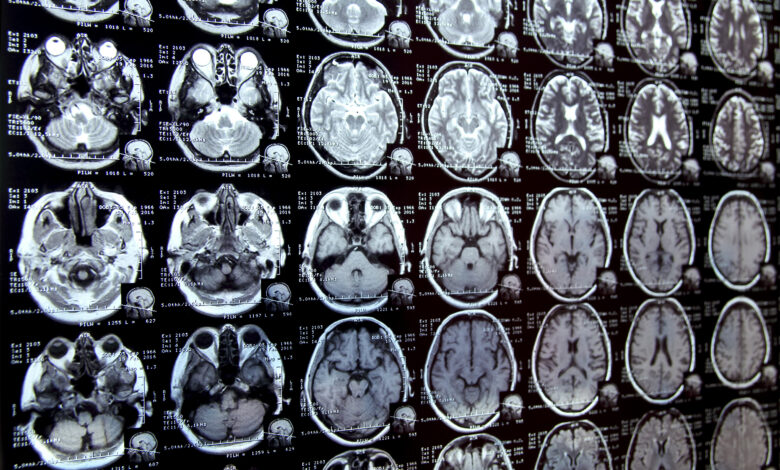

Annotating regions of interest in medical images, a process known as segmentation, is often one of the first steps clinical researchers take when running a new study involving biomedical images.

For instance, to determine how the size of the brain’s hippocampus changes as patients age, the scientist first outlines each hippocampus in a series of brain scans. For many structures and image types, this is often a manual process that can be extremely time-consuming, especially if the regions being studied are challenging to delineate.

To streamline the process, MIT researchers developed an artificial intelligence-based system that enables a researcher to rapidly segment new biomedical imaging datasets by clicking, scribbling, and drawing boxes on the images. This new AI model uses these interactions to predict the segmentation.